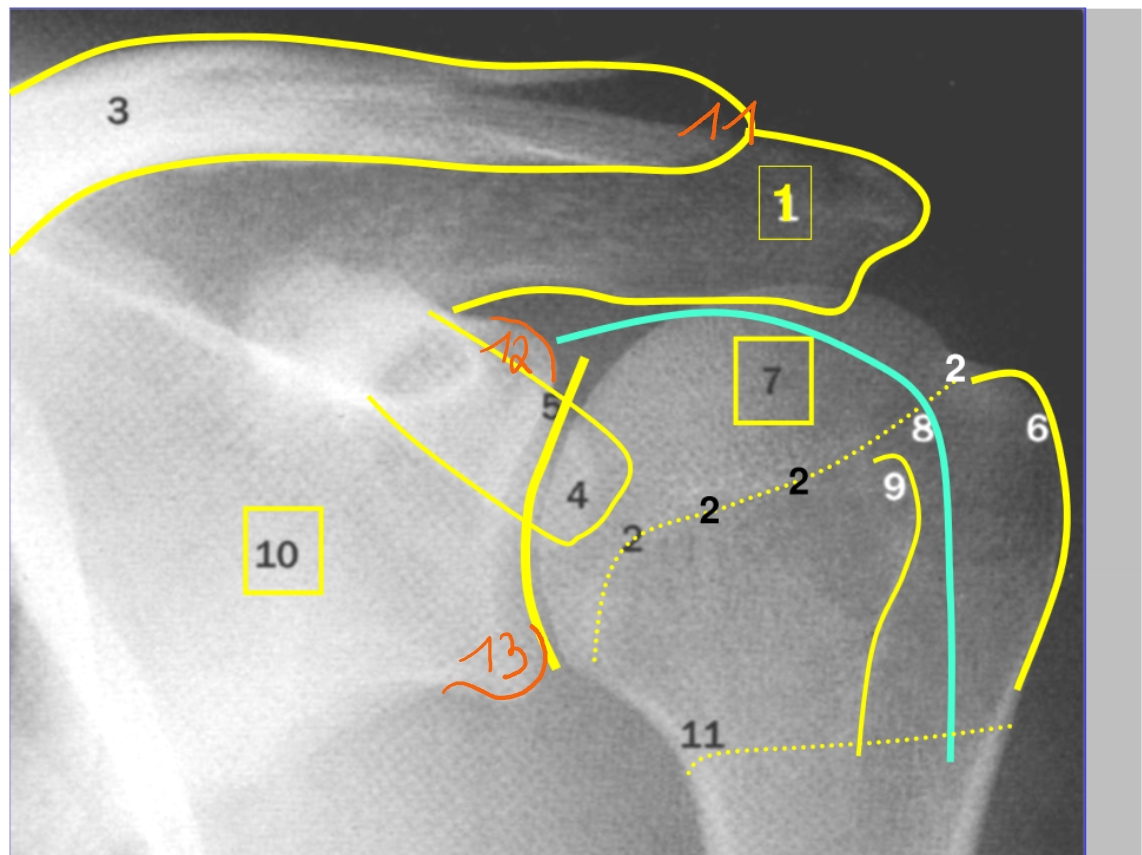

acromion

collum anatomicum

clavicula

processus coracoideus

gleno-humerale gewricht

tuberculum majus

caput humeri

caput longum m. biceps → in de sulcus intertubercularis

tuberculum minus

scapula

acromio-claviculaire gewricht

tuberculum supraglenoidale

tuberculum infraglenoidale

→ linker schouder